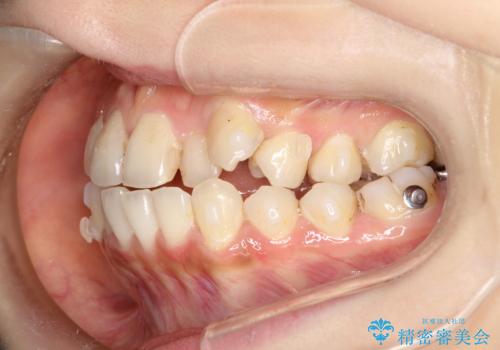

八重歯をインビザラインで非抜歯矯正

- 八重歯を主訴に来院されました。

インビザラインにて奥歯を後方に移動して八重歯が入るスペースを確保してく矯正する計画としました。

八重歯と前歯のガタガタがなくなり、歯並びがきれいになったのと、かみ合わせも改善することができました。